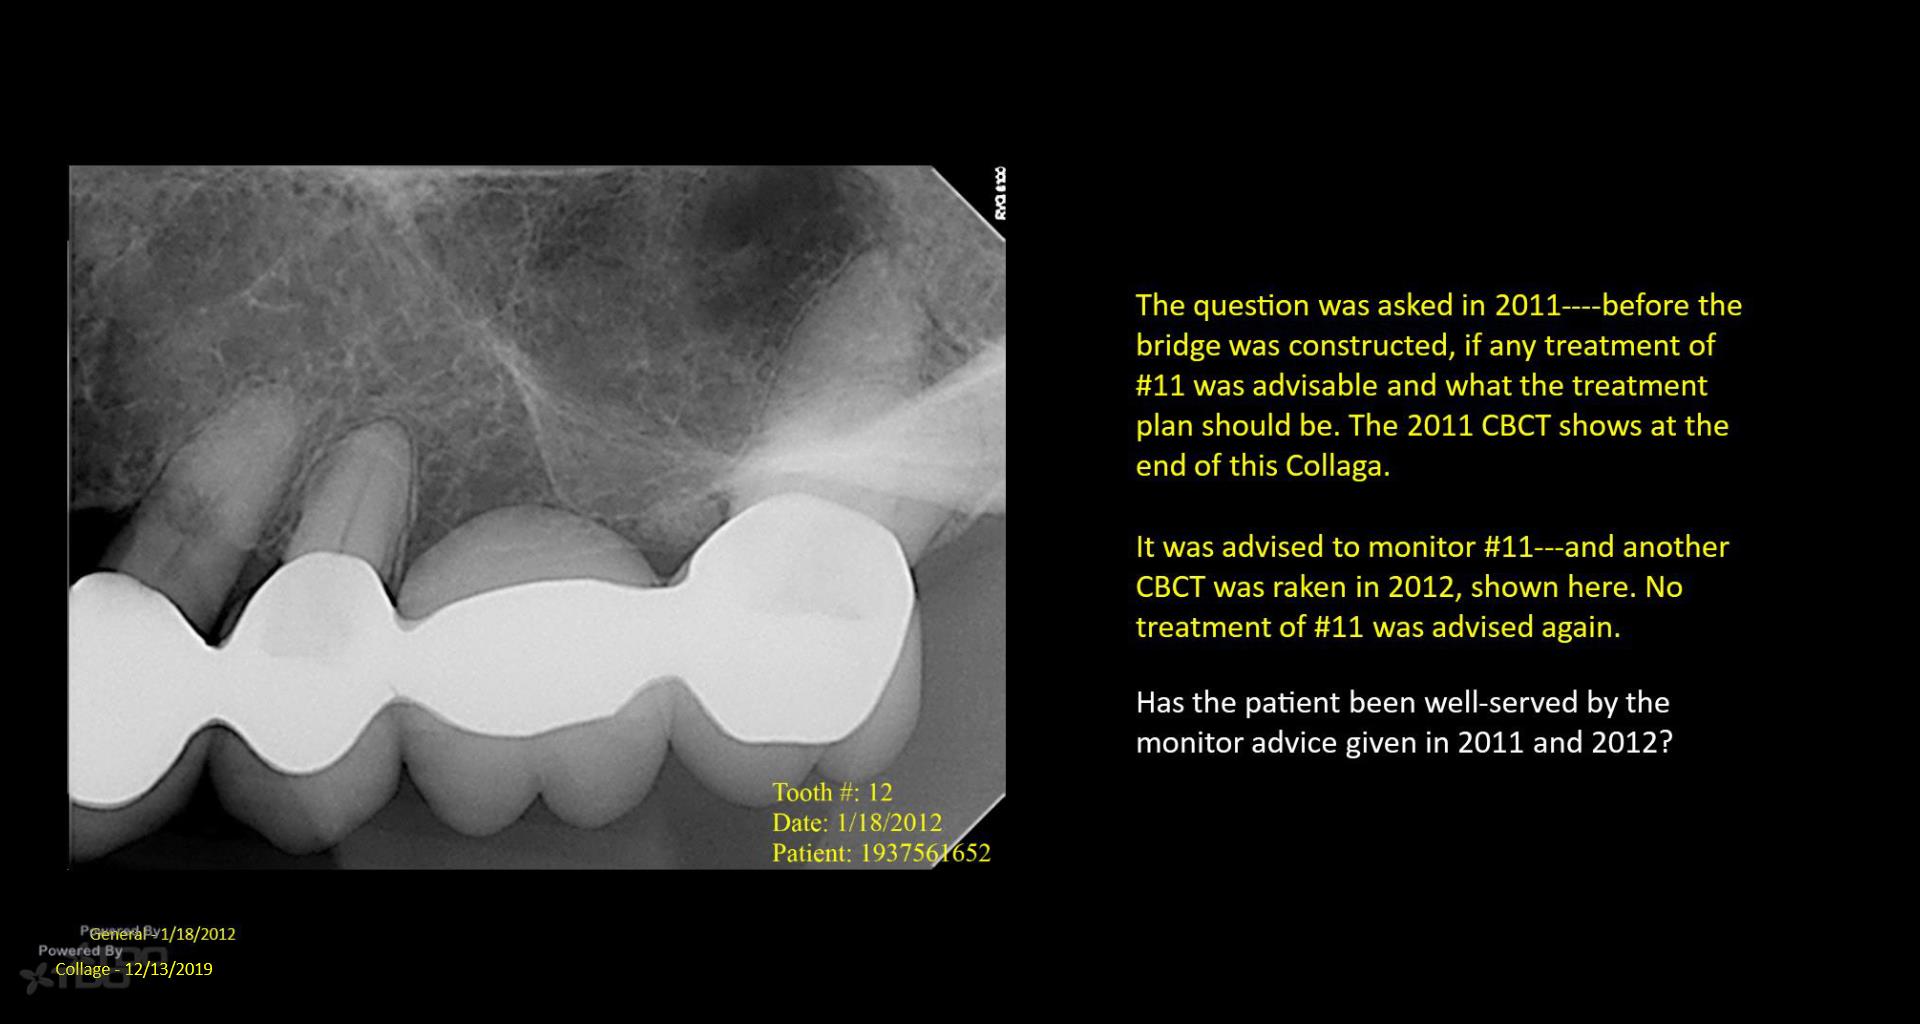

I posted this last month after the consult. There was mixed TDO advice—some said “do it” and others said monitor. Reluctantly, I did it Monday. I couldn’t really address the ECIR that was sub-osseous without removing way too much bone. I just hit it with the Pear Diamond as well as I could. Time will tell if it was a fool’s errand. I video’d the whole thing but don’t have the time to edit it. gbc